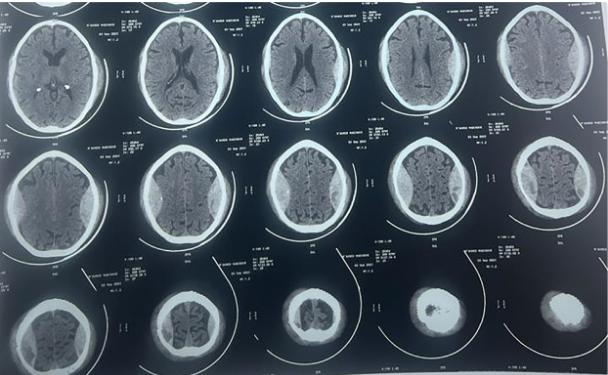

计算机断层扫描(CT)显示双侧对称的顶叶EDH,右侧为25mm,左侧为23.5 mm,少数右侧顶骨下沟回有蛛网膜下腔出血[图1]。骨窗显示双顶骨骨折线[图2]。

图2、轴向骨切片显示左右顶骨骨折